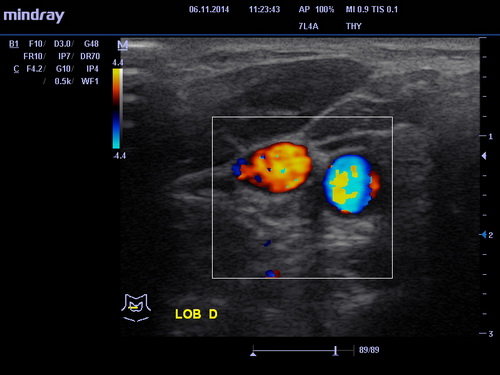

УЗИ щитовидной железы

Узловой зоб – появляются твердые узлы в тканях щитовидной железы.

Киста – полость с жидкостью. Может быть как врождённой, так и приобретённой.